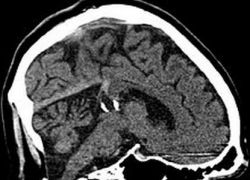

Киста шишковидной железы головного мозга. Описание

Киста шишковидной железы головного мозга считается явлением достаточно редким. Согласно статистике, данное нарушение отмечается в полутора процентах всех случаев патологии органа.